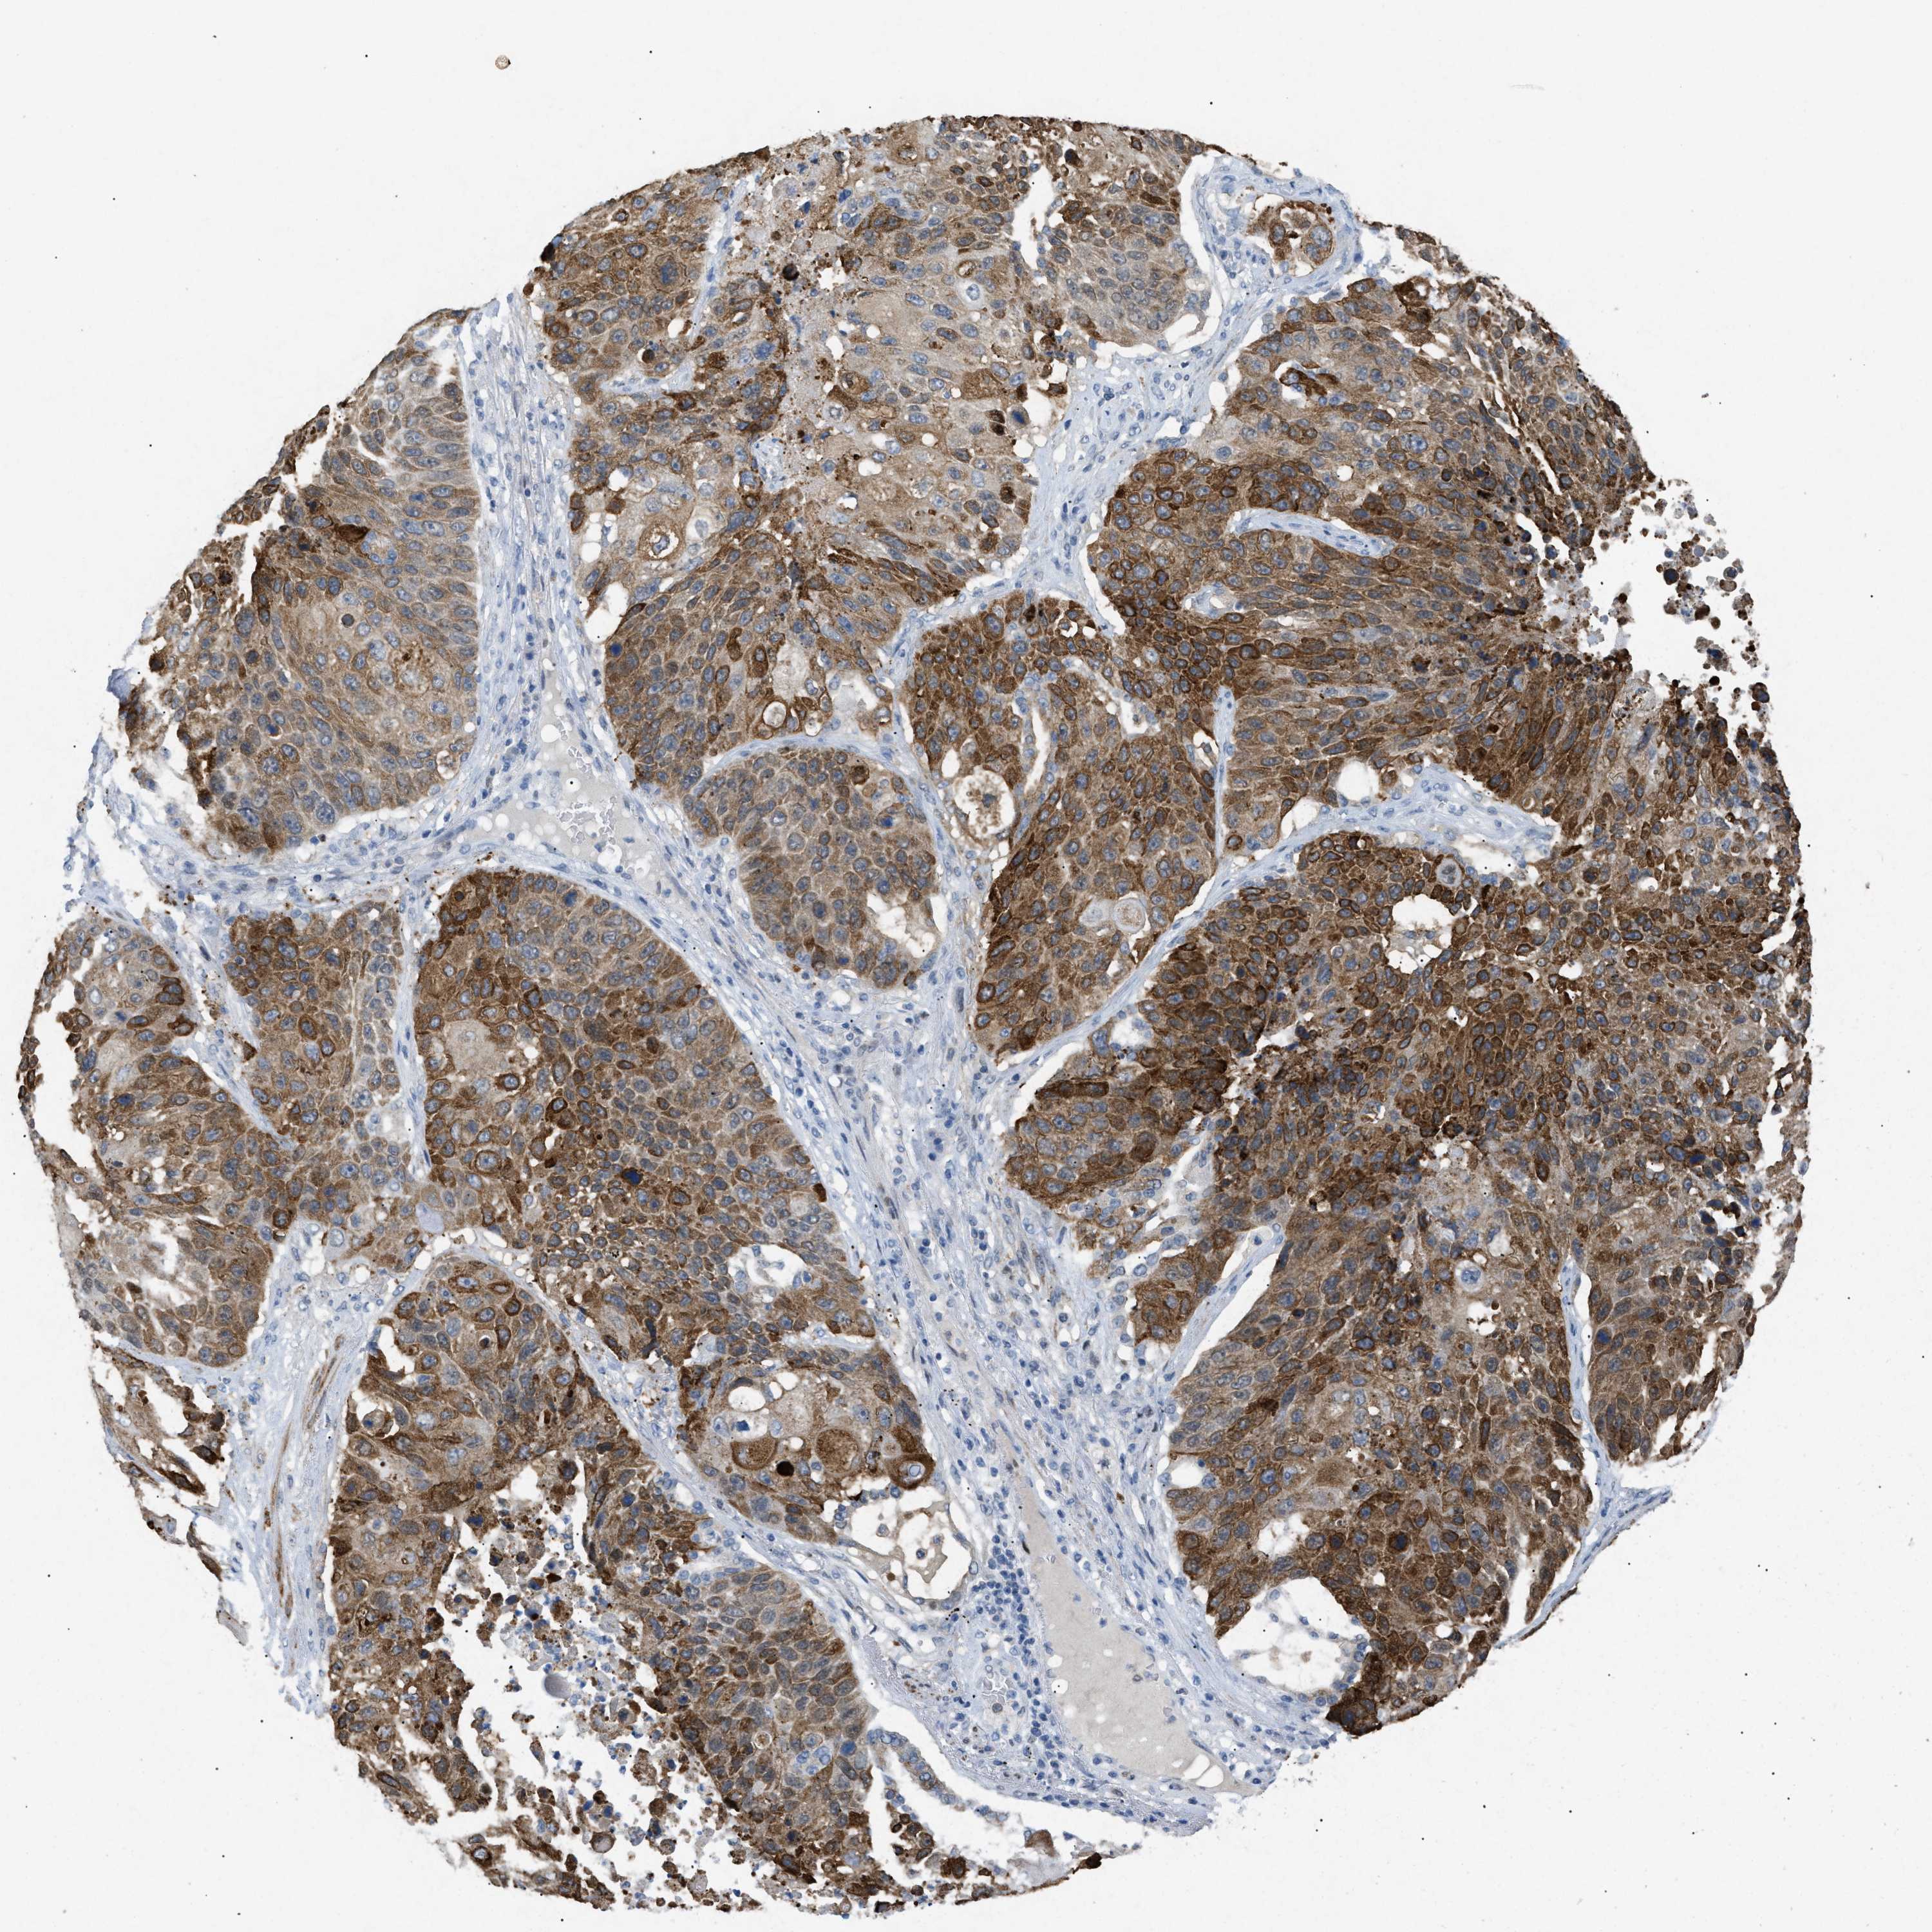

CANCER LUNG CANCER Show tissue menu

LUAD TCGA LUAD VALIDATION LUSC TCGA LUSC VALIDATION PROTEIN LUAD CPTAC PROTEIN LUSC CPTAC PROTEIN EXPRESSION